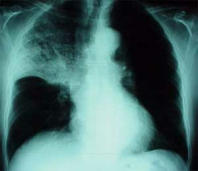

Blood group A has a chronic mucus problem that provokes that the members of type A are always in danger for infection diseases: Sinusitis, bronchitis and pneumonia.

Example: x-ray photo of a pneumonia with shadowed medium and upper part of the lung (right).